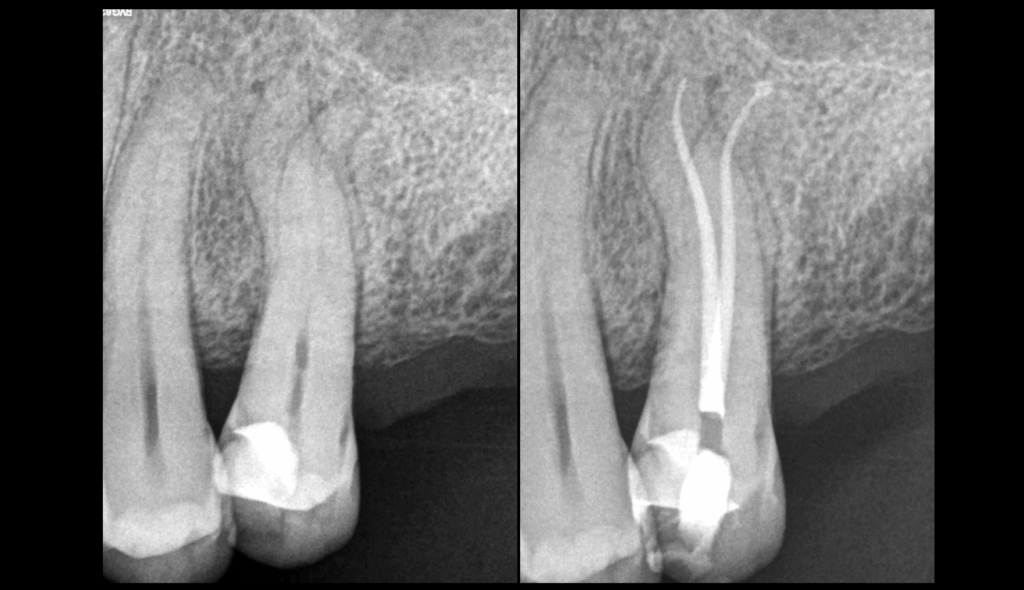

🎯 Courbures légères & oblitérations canalaires